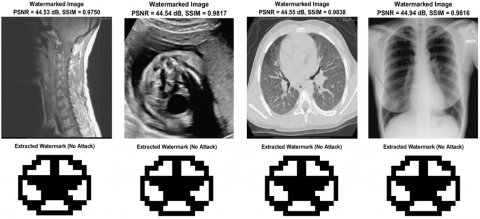

The proposed approach is evaluated through visual and numerical analyses to assess imperceptibility and robustness. For privacy preservation, the watermark must remain undetectable. Established thresholds define this requirement: a peak signal-to-noise ratio (PSNR) of ≥29dB indicates high image quality, while values <25dB suggest visible degradation [26]. Similarly, a structural similarity index (SSIM) of ≥0.90 ensures perceptual invisibility [27]. As indicated in Figures 7(a) and 7(b), our watermarking method achieves strong imperceptibility, demonstrated by an average PSNR of 44.90dB -ranging from 44.84 to 44.93dB- across 115 test images. This high PSNR, combined with an SSIM exceeding 0.9827 -ranging from 0.9783 to 0.9867-, confirms that the method introduces modifications indistinguishable to human observers. Figure 8 exemplifies this imperceptibility across diverse medical imaging modalities, showing watermarked images (top row) that maintain excellent visual quality with PSNR values consistently above 44dB and SSIM values exceeding 0.98, while the corresponding extracted watermarks (bottom row) demonstrate perfect recovery without any attack scenarios. The near-ideal SSIM values further ensure the preservation of critical diagnostic details-a necessity in medical imaging, where even minor alterations risk clinical misinterpretation. In comparative evaluations, as indicated in Table 1, our method demonstrates superior imperceptibility performance across diverse medical imaging modalities. For X-ray images using the COVID-19 Radiography dataset, our approach achieves a PSNR of 44.94 dB, outperforming Saïd et al. [27] (38.74 dB), Fares et al. [4] (44.98 dB), and Hebbache et al. [1] (44.23 dB). Across CT, MRI, and ultrasound images from the MedPix dataset, our method consistently delivers competitive performance with PSNR values of 44.55 dB, 44.53 dB, and 44.54 dB respectively, significantly surpassing Saïd et al. [27] (39.85 dB and 39.38 dB for CT and MRI) while maintaining comparable quality to Hebbache et al. [1] (44.23dB across all modalities).

Figure 8. Watermarked images and their extracted watermarks without any attack